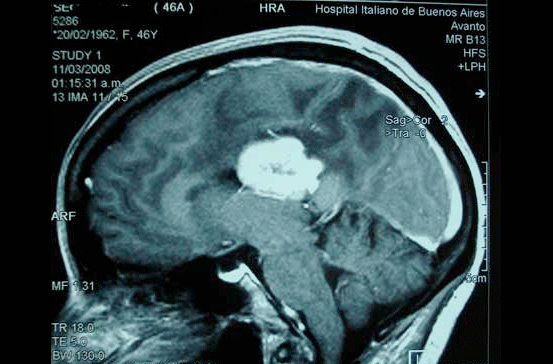

2. El daño cerebral adquirido se considera a cualquier tipo de lesión o cambios que sufre el cerebro por el que surgen alteraciones en el funcionamiento normal, bien por un traumatismo craneal, una isquemia (también conocida por ictus, accidente cerebro-vascular, infarto cerebral), tumores cerebrales, hidrocefalias, anoxias,

1. tumores cerebrales

1. Tumores